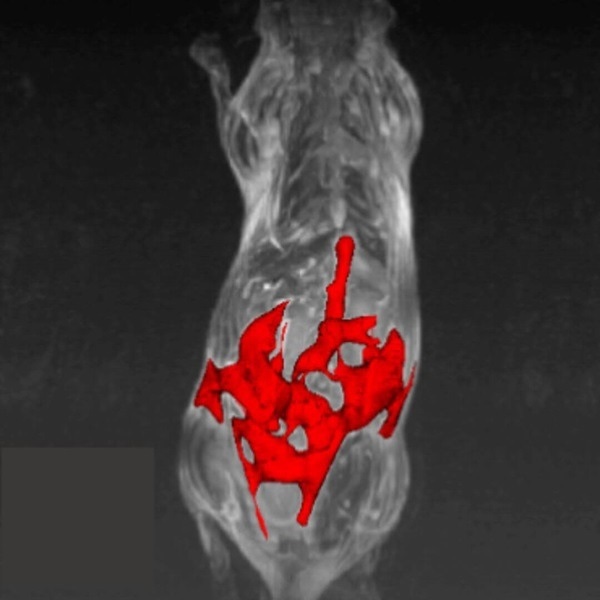

Hindlimb tumor growth: Monitoring the growth of xenograft tumor grown in the mouse hindlimb is identified with T2-weighted images. Segmentation of tumor region of interests (in red) on each tumor-containing slice allows accurate volume quantification. Image Credit: Scintica Instrumentation Inc

Monitoring the growth of xenograft tumor grown in the mouse hindlimb is identified with T2-weighted images. Segmentation of tumor region of interests (in red) on each tumor-containing slice allows accurate volume quantification. Image Credit: Scintica Instrumentation Inc